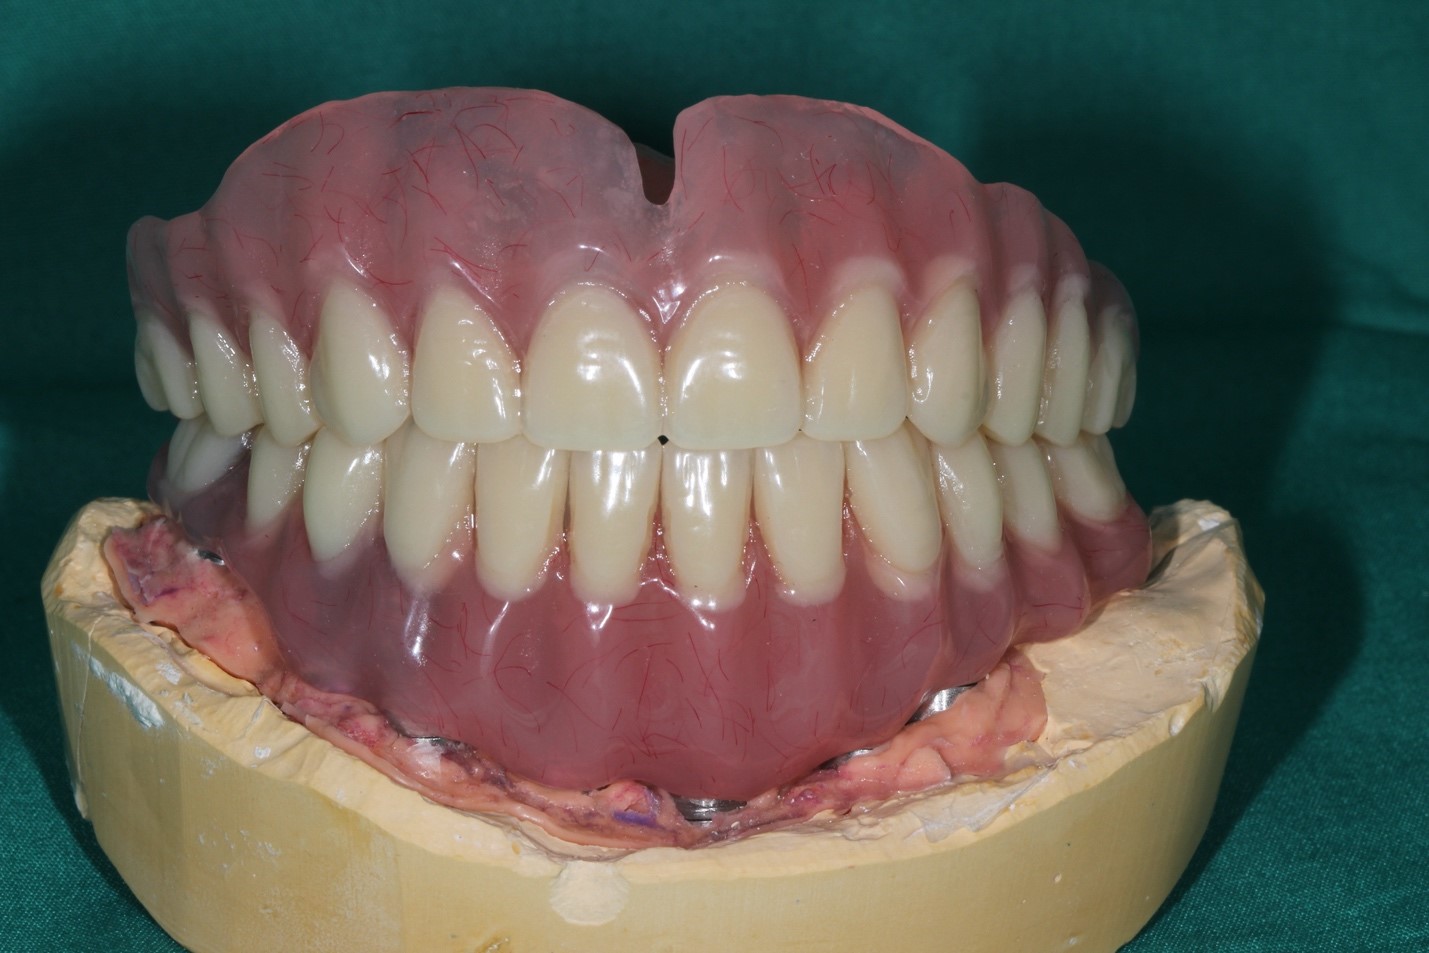

Далее импланты интегрировались и мы стали делать постоянный протез:

Далее поверх этого металла мы нарастили керамику, стало вот так:

Это контроль промывных пространств, окончательные протезы, окончательный внешний вид

На этой стадии пациент мог весело улыбаться, открывать пиво зубами (не рекомендуется, но технически мог бы), жевать стейк любой прожарки без усилий и в экстренных ситуациях перекусывать во рту металлический кабель сечением до 12 мм без особых последствий (строго не рекомендуется, даже на спор). Металлы основания конструкции — кобальт и хром. Обычно альтернатива металлокерамике — титановый каркас и цирконий, но в данной ситуации из-за геометрии такой сборки возможности её использовать почти не было, и выбрали керамику на кобальт-хроме. К титану керамика не крепится, не удерживается. Десна, естественно, не могла быть восстановлена, поэтому она фактически нарисована на керамике — это так называемая высокоэстетичная конструкция, то есть при разговоре можно и не догадаться, что зубы ненатуральные (если вы не врач).